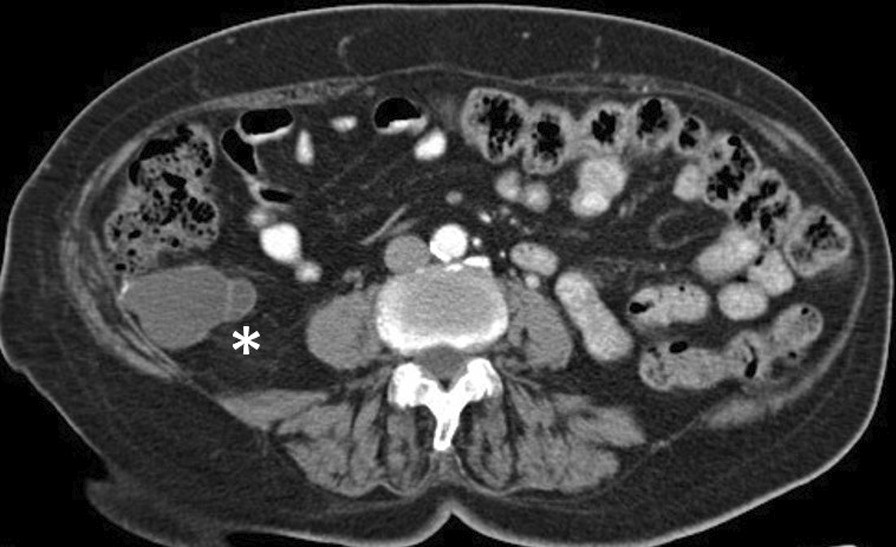

CT scan showing low-grade appendiceal mucinous neoplasms with liquid density adjacent to the caecum and retrocecum (*)